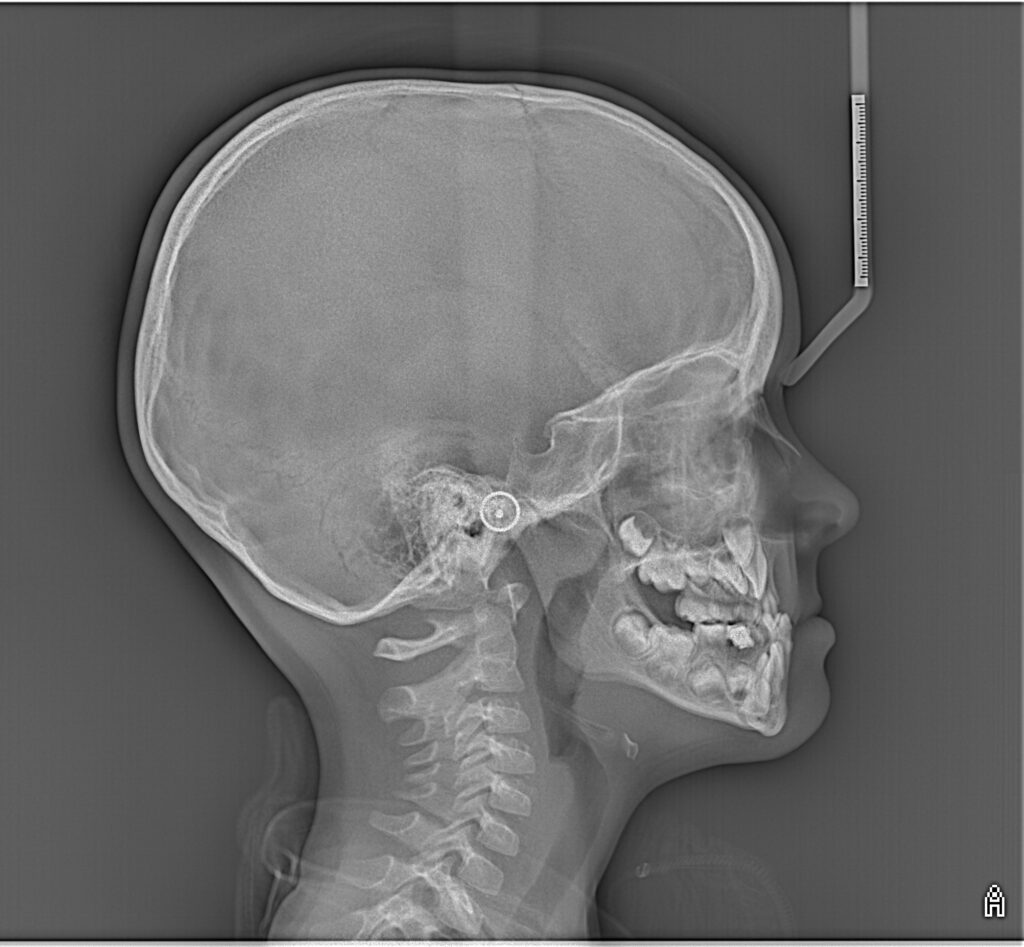

Ортопантомограмма – це велике зображення, яке дає нам загальну картину стану щелеп та зубів, а також оточуючих тканин: кісткова тканина, верхньощелепні пазухи, скронево-нижньощелепні суглоби. Це надзвичайно цінний рентгенологічний скринінг-тест, який дозволяє провести раннє виявлення патологічних змін.

Ортопантомографічне зображення необхідне для встановлення правильного діагнозу та розробки плану лікування.

Ортопантомографія